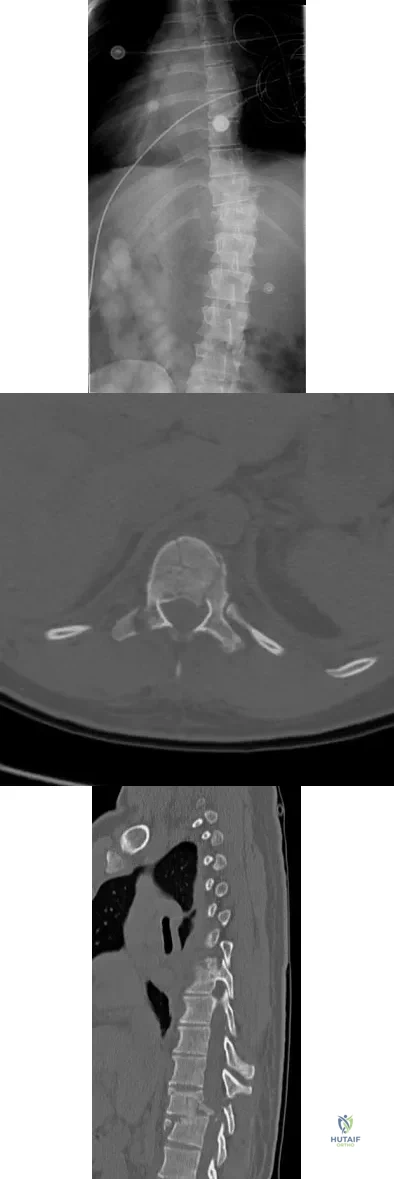

An otherwise healthy 70-year-old man has back and bilateral leg pain in an L5 distribution that is aggravated by standing more than 10 minutes or walking more than 100 feet. He has to sit to get relief. Neurologic and pulse examinations are normal. A radiograph and MRI scan are shown in Figures 4a and 4b. Treatment should consist of

Explanation